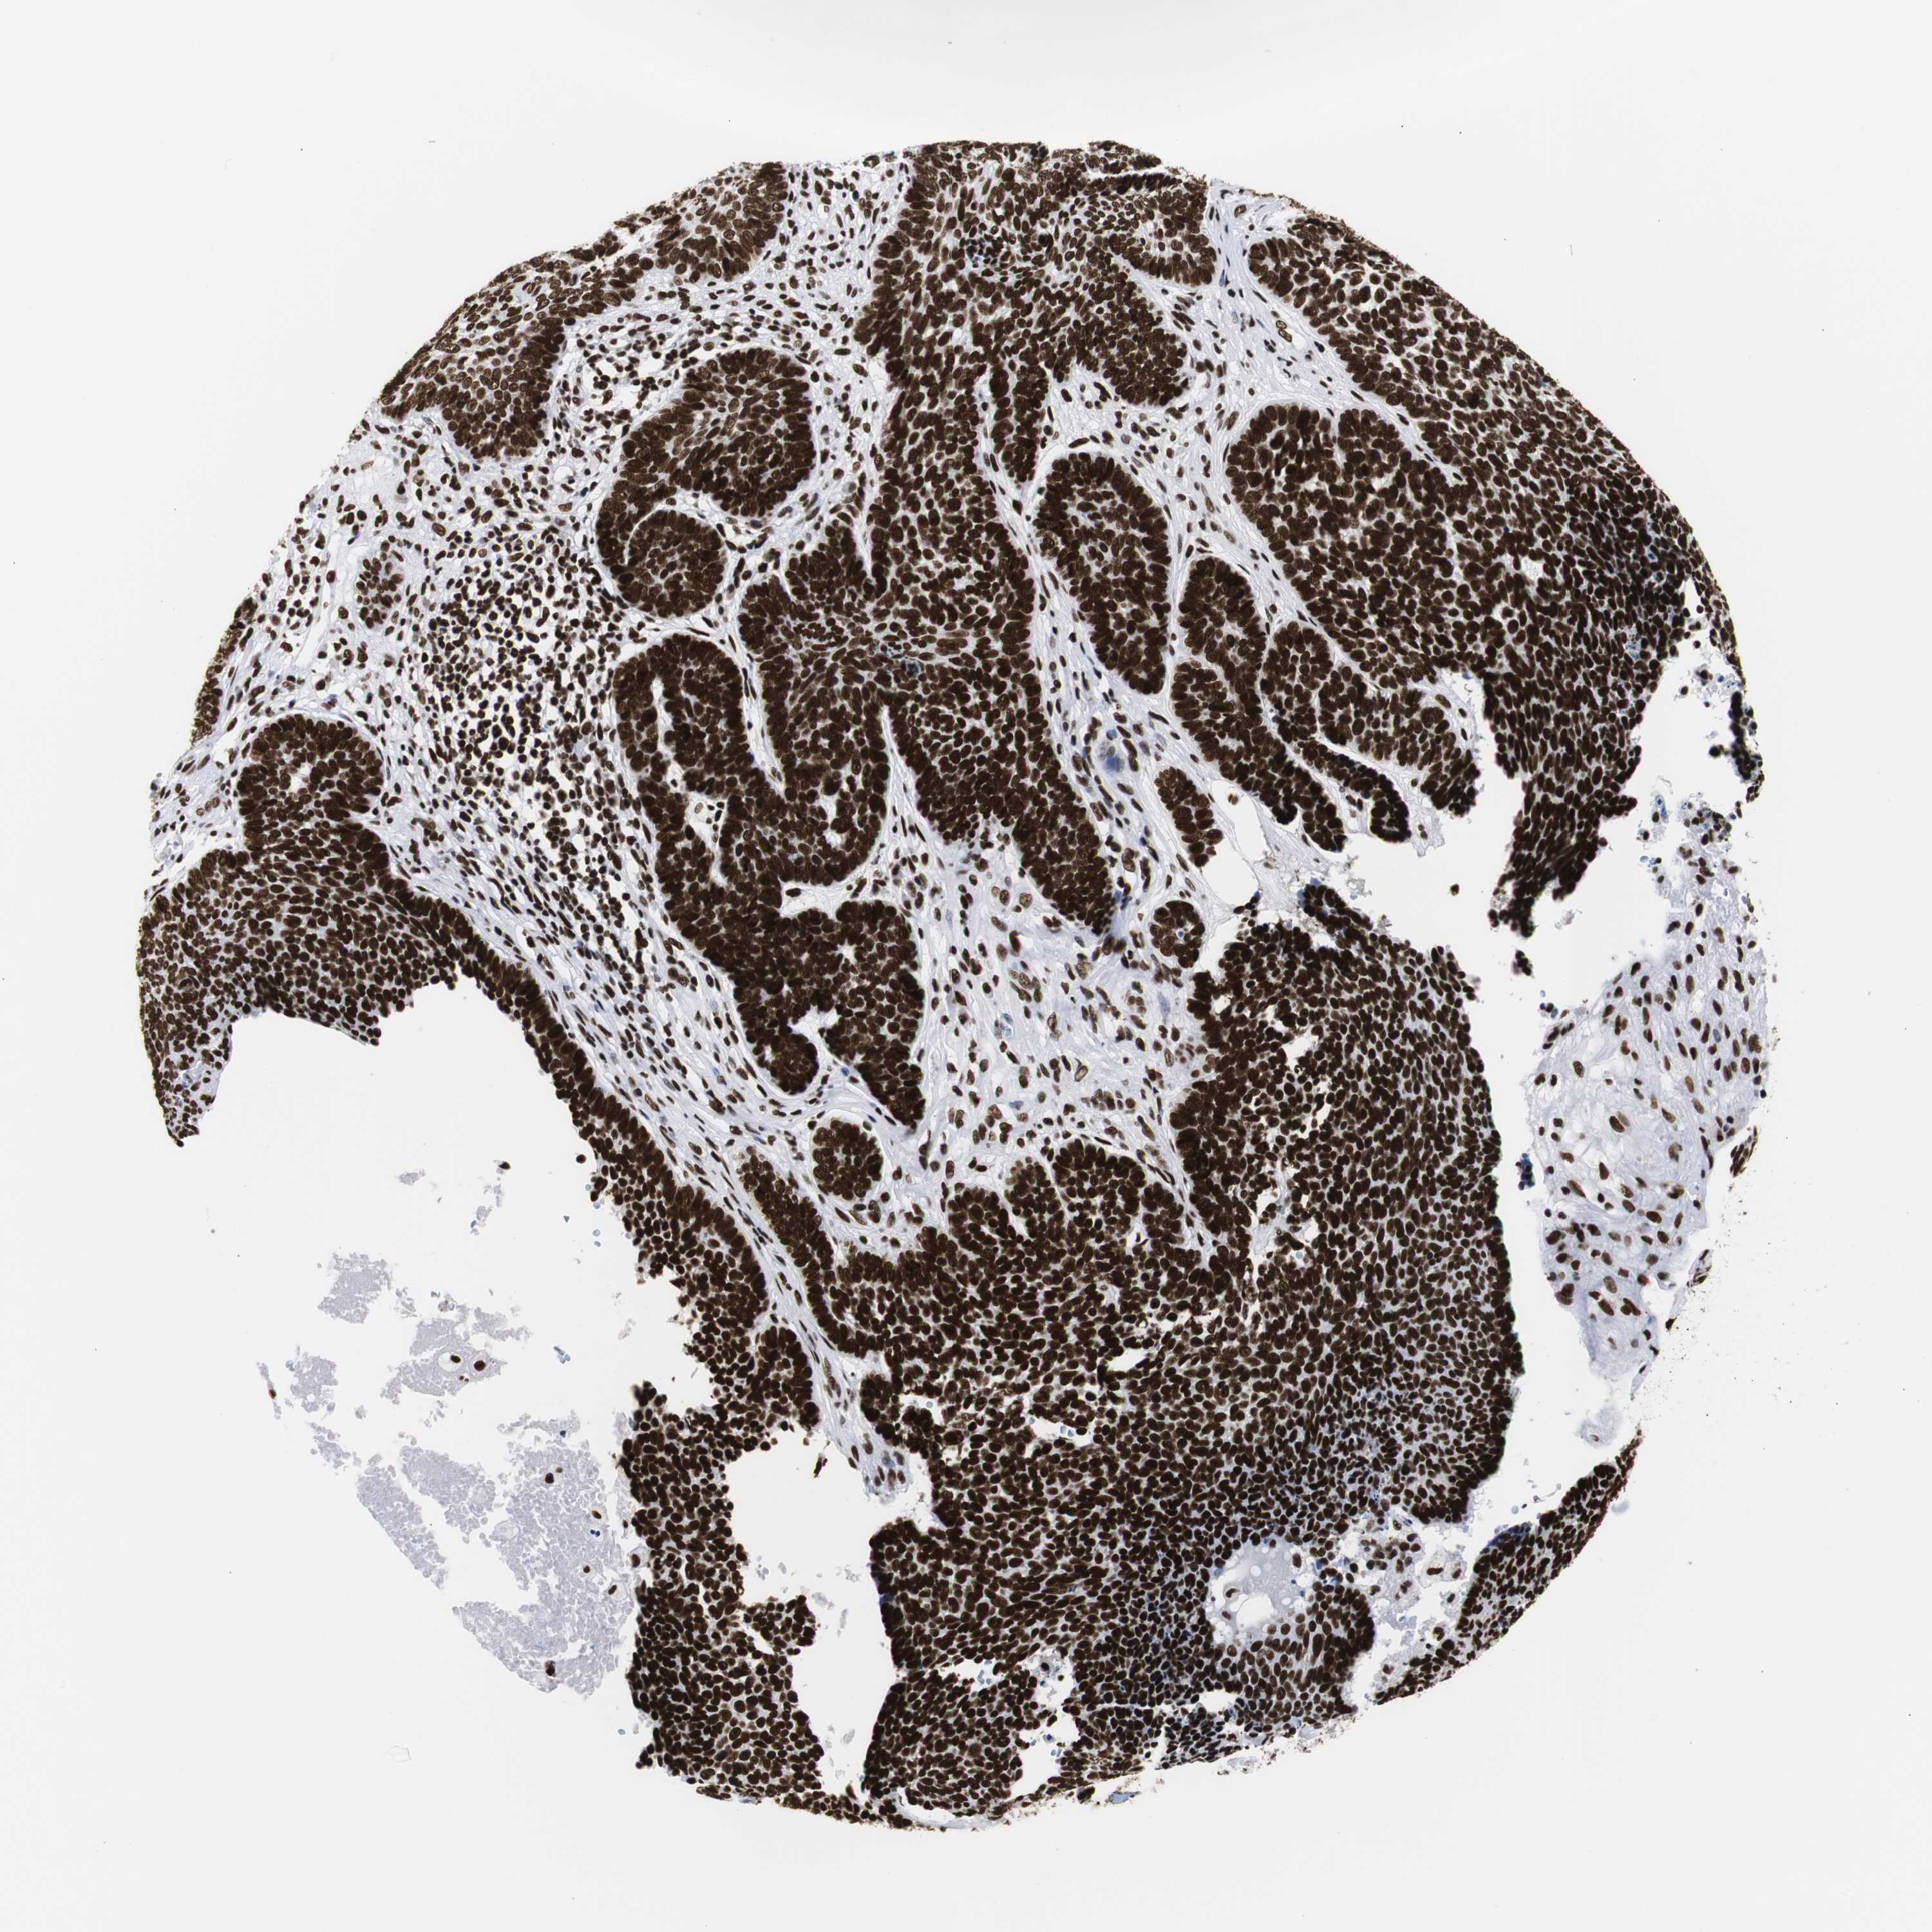

SKIN CANCER - Protein expressioni

A mouse-over function shows sample information and annotation data. Click on an image to view it in a full screen mode. Samples can be filtered based on level of antibody staining by selecting one or several of the following categories: high, medium, low and not detected. The assay and annotation is described here.

Each image is clickable and will lead to virtual microscopy that enables deeper exploration of all samples and also displays staining intensity scores, fraction scores and subcellular localization as well as patient and tissue information for each sample.

Antibody HPA016884

Staining

High

Medium

Low

Not detected

Intensity

Strong

Moderate

Weak

Negative

Quantity

>75%

75%-25%

<25%

None

Location

Nuclear

Cytoplasmic/membranous

Cytoplasmic/membranous,nuclear

Squamous cell carcinoma, NOS

Basal cell carcinoma

Squamous cell carcinoma in situ, NOS

Squamous cell carcinoma, metastatic, NOS

Adnexal tumor, benign

Papilloma, NOS